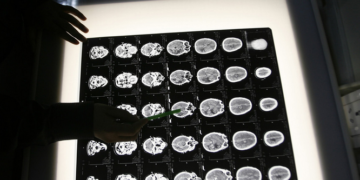

DevamıDünya çapında yapılan araştırmalara rağmen Alzheimer hastalığı hâlâ kapalı bir kutu. Cevabı yapay zekanın bulacağına inanan bilim insanları, Alzheimer’ı beyindeki küçük yapısal değişikleri gözlemleyerek 10 yıl önce...